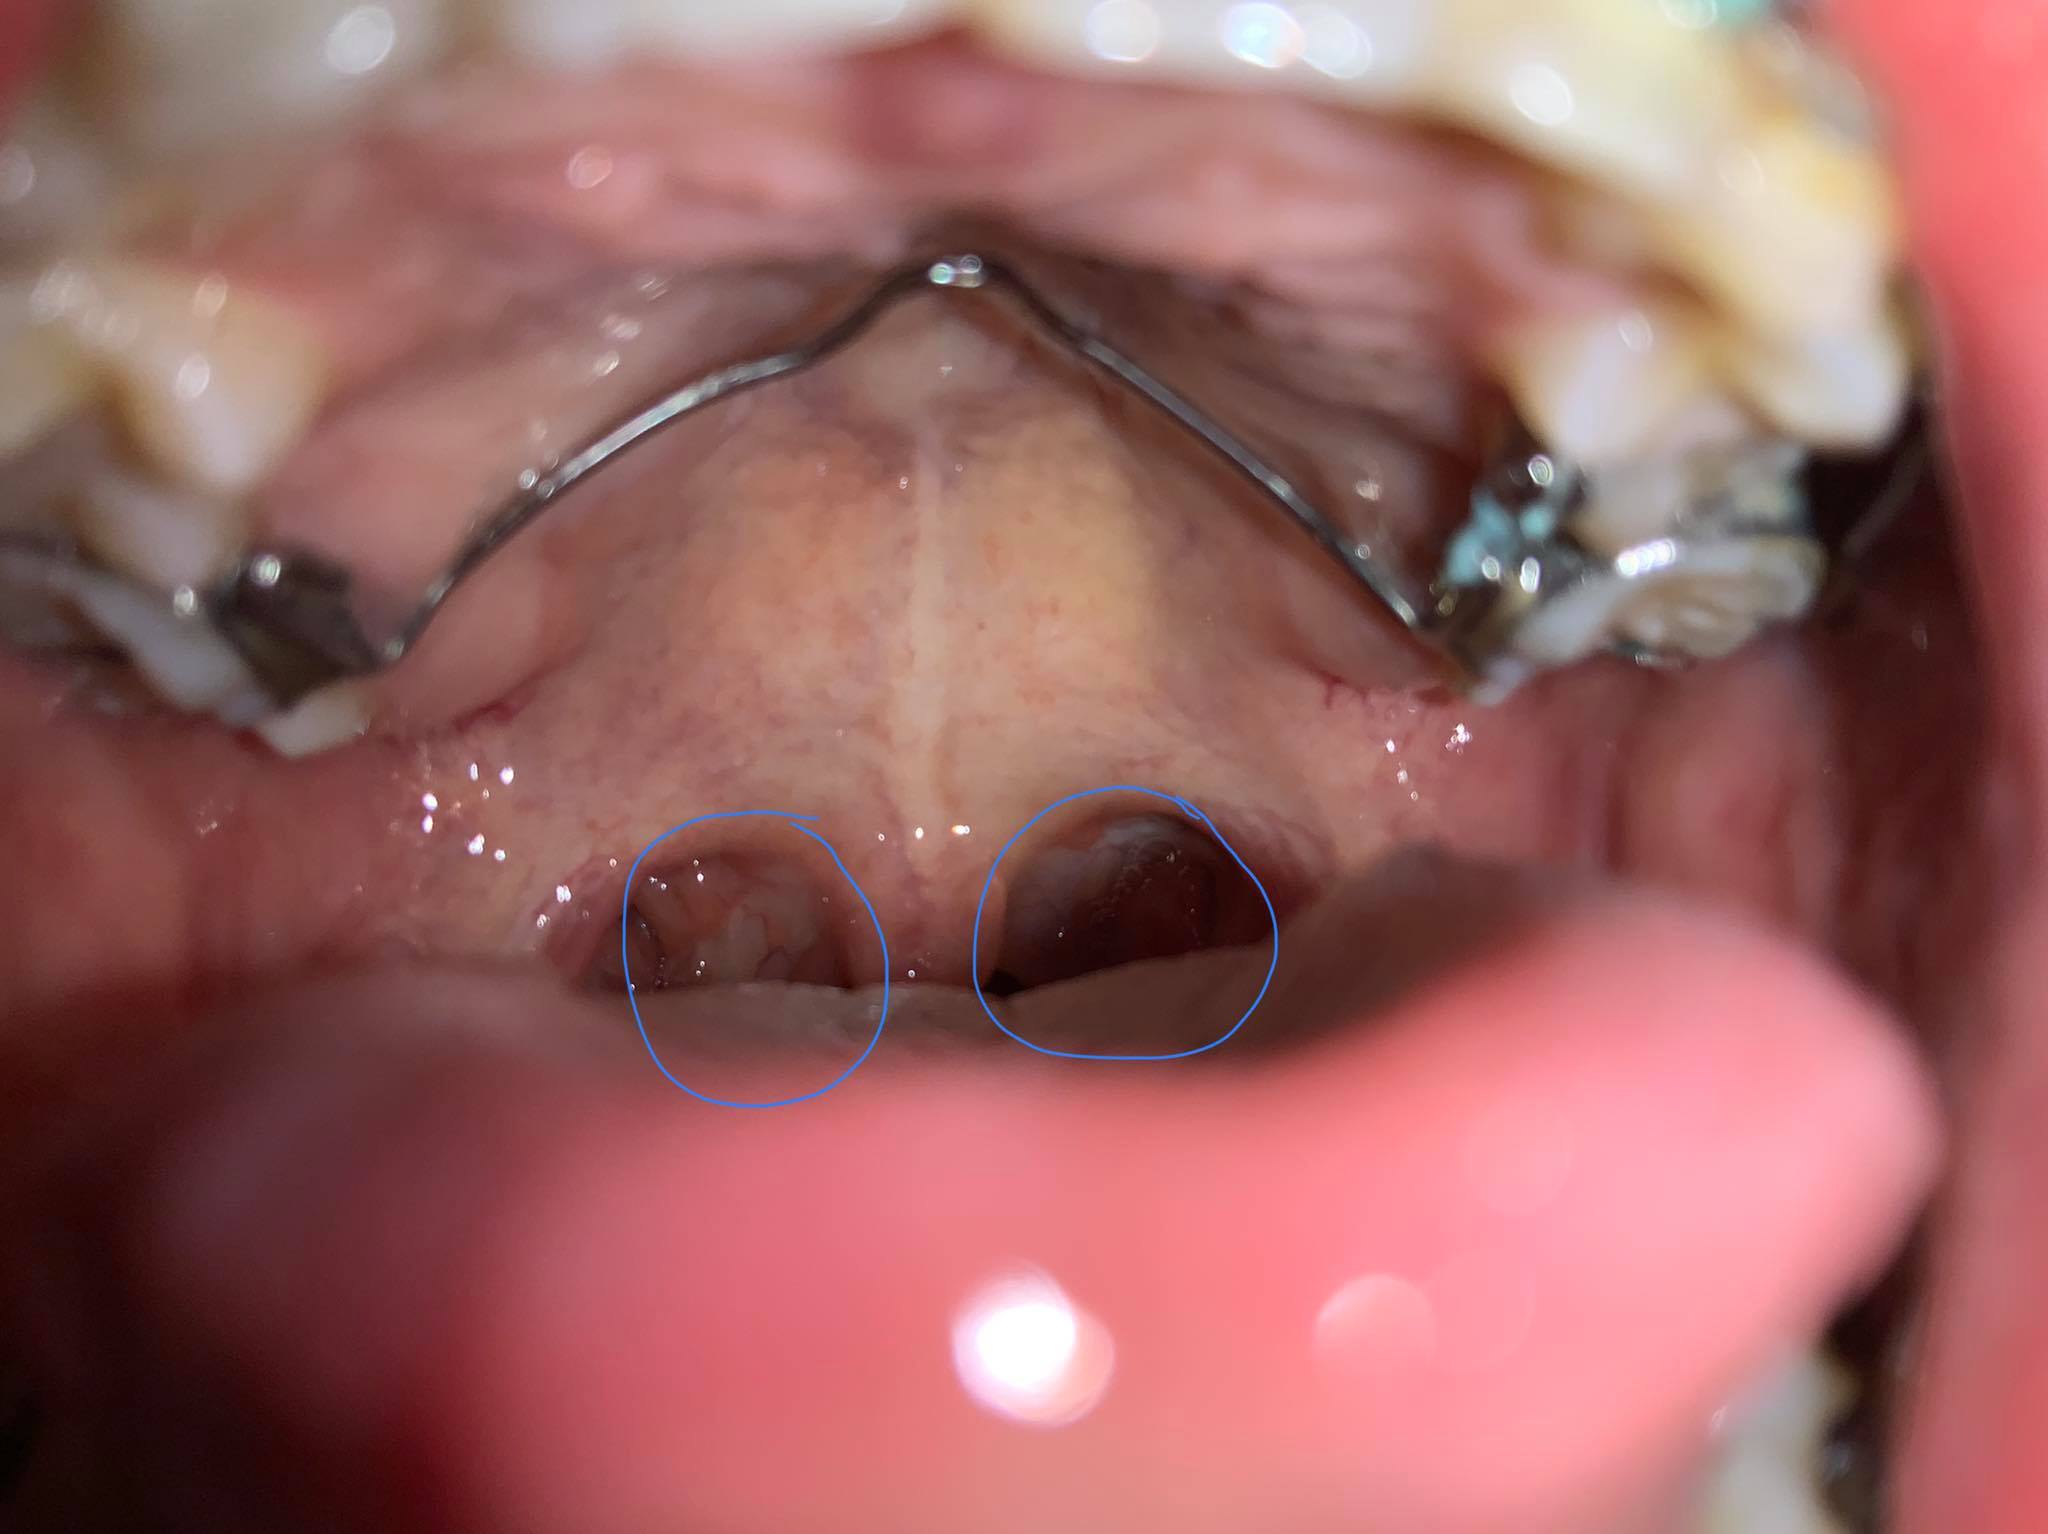

เหมือนมีอะไรขาวๆอยู่ในคอ เป็นมา 3 สัปดาห์แล้วไม่หายสักที

เหมือนมีอะไรขาวๆอยู่ในคอครับ แรกๆเริ่มจากเจ็บคอ พอกลืนแล้วก็เจ็บ ผ่านไป 3-4 วัน อาการเจ็บคอดีขึ้น แต่ ไอขาวๆยังไม่หายครับ เป็นมา 3 สัปดาห์ ไปหาหมอ หมอให้ยาฆ่าเชื้อมากิน แล้วยังไม่หาย ผมควรทำยังไงดีครับ มันรำคาญมาก